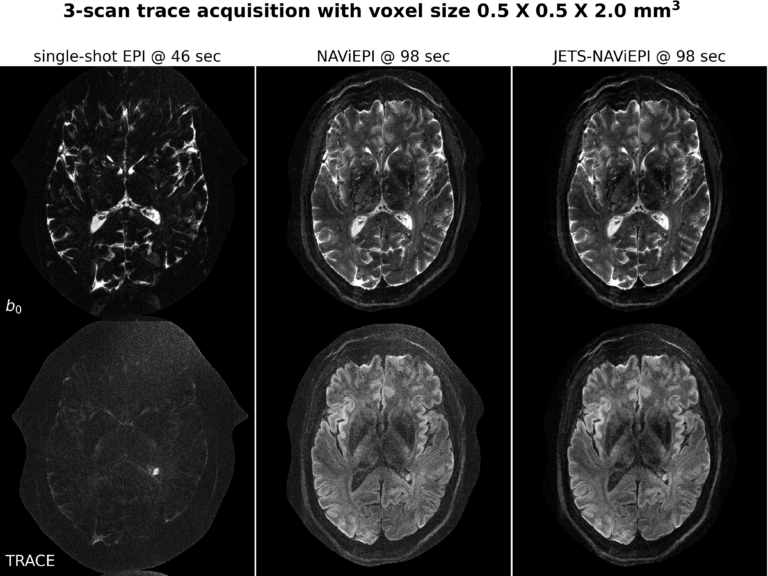

We are very happy to announce that our most recent manuscript (https://doi.org/10.1162/imag_a_00085) has just been published in early view in Imaging Neuroscience. We introduced a novel diffusion MRI acquisition and reconstruction approach for ultra-high field (7T) imaging. Our method consists of a ...